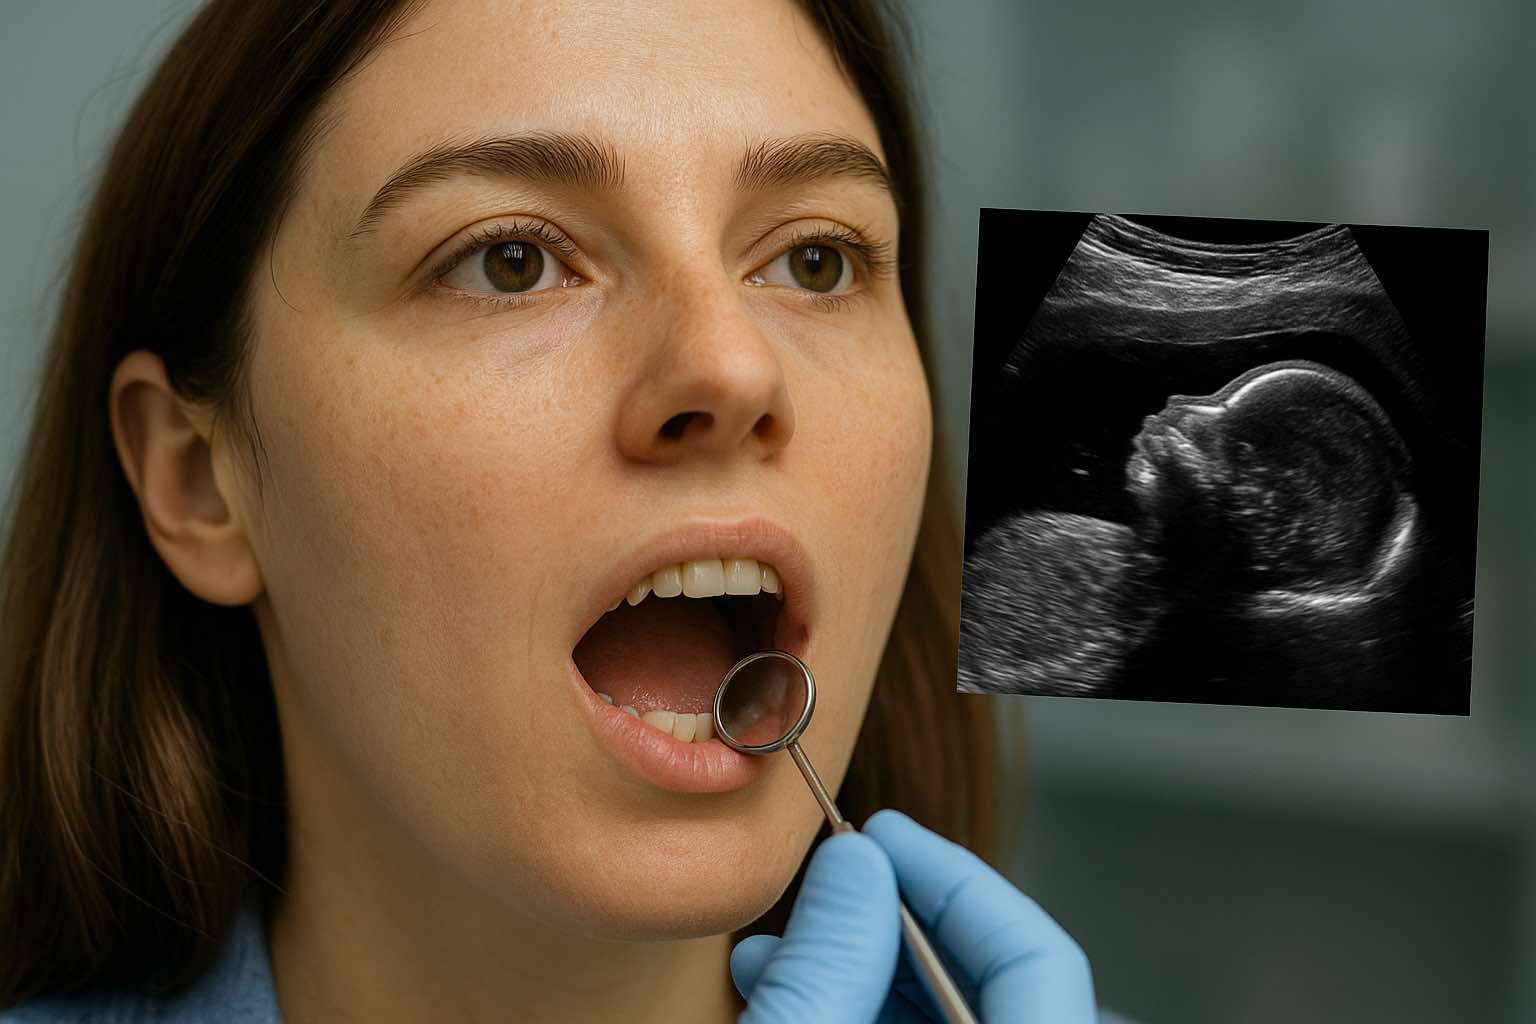

Fogászati betegségek és a termékenységi problémák közötti kapcsolat

termékenységi problémák a párok ~10–15%-át érintik világszerte, és nem csak női okokra vezethetők vissza. Becslések szerint az infertilitással küzdő párok ~40%-ánál elsődlegesen férfi eredetű a probléma researchgate.net. A meddőség okainak felkutatása során azonban a szájüreg állapotát gyakran figyelmen kívül hagyják oraldna.comÚjabb kutatások rávilágítottak arra, hogy a krónikus fogászati betegségek – különösen a fogágybetegség, a fog eredetű ciszták és tályogok, illetve az ún. “gócos fogak” (krónikus gyulladásos gócot hordozó fogak) – hozzájárulhatnak a termékenység romlásához. A fogíny és a fogágy gyulladása révén ugyanis a káros baktériumok átjuthatnak a száj lokális védőgátján, bekerülhetnek a véráramba, és távoli szerveknél is káros folyamatokat indíthatnak el researchgate.netoraldna.com. A tartós bakteriális terhelés és a vele járó gyulladásos mediátorok jelenléte potenciálisan károsítja a reproduktív rendszert, gátolhatja a fogantatást, sőt a korai terhesség kimenetelét is negatívan befolyásolhatja researchgate.net.

Számos vizsgálat utal arra, hogy a krónikus fogágybetegség negatívan befolyásolhatja a nők termékenységét. Egy ausztráliai multicentrikus, randomizált klinikai vizsgálat (SMILE Study, 2012) kimutatta, hogy fogínygyulladásban vagy fogágybetegségben szenvedő nőknél átlagosan 7,1 hónap szükséges a fogantatáshoz, szemben az egészséges fogazatú nők 5 hónapos átlagos fogantatási idejével researchgate.net. Ez alapján a súlyos parodontális gyulladás jelenléte kb. két hónappal meghosszabbíthatja a teherbeeséshez szükséges időt (különösen nem kaukázusi etnikumú nők esetén, akiknél a vizsgálatban gyakoribb volt a periodontitis) researchgate.net. Ezt a trendet alátámasztja egy prospektív kohorszvizsgálatis, melyben 256 finn nő fogamzási esélyeit követték nyomon 12 hónapon át. Ebben a vizsgálatban jelentősen gyakrabban mutatták ki a Porphyromonas gingivalis baktérium jelenlétét a nyálmintákban azoknál a nőknél, akiknek nem sikerült teherbe esniük, mint akiknél sikerült (8,3% vs. 2,1%) dental-tribune.com. Sőt, azoknál a nőknél, akik nyálában P. gingivalis volt kimutatható és a baktérium ellen magas ellenanyagszint volt mérhető, háromszoros kockázattal (hazard ráta ~3) maradt el a fogantatás 12 hónapon belül az ilyen baktériumot nem hordozó társaikhoz képest dental-tribune.comsciencedaily.com – függetlenül az egyéb befolyásoló tényezőktől (életkor, dohányzás, szocioökonómiai státusz, bakteriális vaginózis, stb.) dental-tribune.comsciencedaily.com(Megjegyzés: ez egy humán prospektív megfigyeléses vizsgálat eredménye.) A fenti eredmények alapján a kutatók felhívták a figyelmet arra, hogy már enyhébb fokú fogágy-érintettség – sőt akár klinikailag jelentősebb tünetek nélküli baktériumhordozás – is szisztémás hatásokkal járhat, amelyek rontják a fogamzóképességet dental-tribune.comdental-tribune.com.

A bemutatott kutatási adatok alapján megállapítható, hogy a krónikus fogászati betegségek – különösen a fogágybetegség és a fogászati gócok – potenciális rizikótényezőt jelentenek a termékenységi problémák kialakulásában. Nők esetében a súlyos fogágy-gyulladás összefüggést mutat a fogantatás késlekedésével, illetve bizonyos nőgyógyászati kórállapotokkal (endometriózis, PCOS). Férfiaknál a rossz szájhigiéné és parodontális státusz együtt járhat gyengébb spermium-paraméterekkel és akár erekciós problémákkal is. A lehetséges biológiai magyarázatok két fő csoportra oszthatók: egyrészt a baktériumok közvetlen disszeminációja a szájüregből a reproduktív szervek felé (ami gyulladást és szöveti károsodást okoz ott), másrészt a szisztémás gyulladásos hatás, mely felborítja a normál élettani folyamatokat a fogantatás körül.